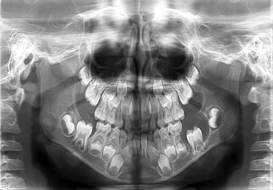

Examen radiológico

Fue indicado y realizado el mismo día de la primera consulta un estudio radiográfico panorámico, donde se observó una imagen radiolúcida en relación con la corona del diente 36 no erupcionado aún. Según cronología de brote dentario y teniendo en cuenta la edad del paciente no correspondía en ese momento.

Dicha imagen se extendía desde las inmediaciones distales de los dientes 75 y 34 incluido hasta la región mesial del diente 37, igualmente incluido. El diente 36 mostraba una formación del primer tercio apical. (Fig. 2).